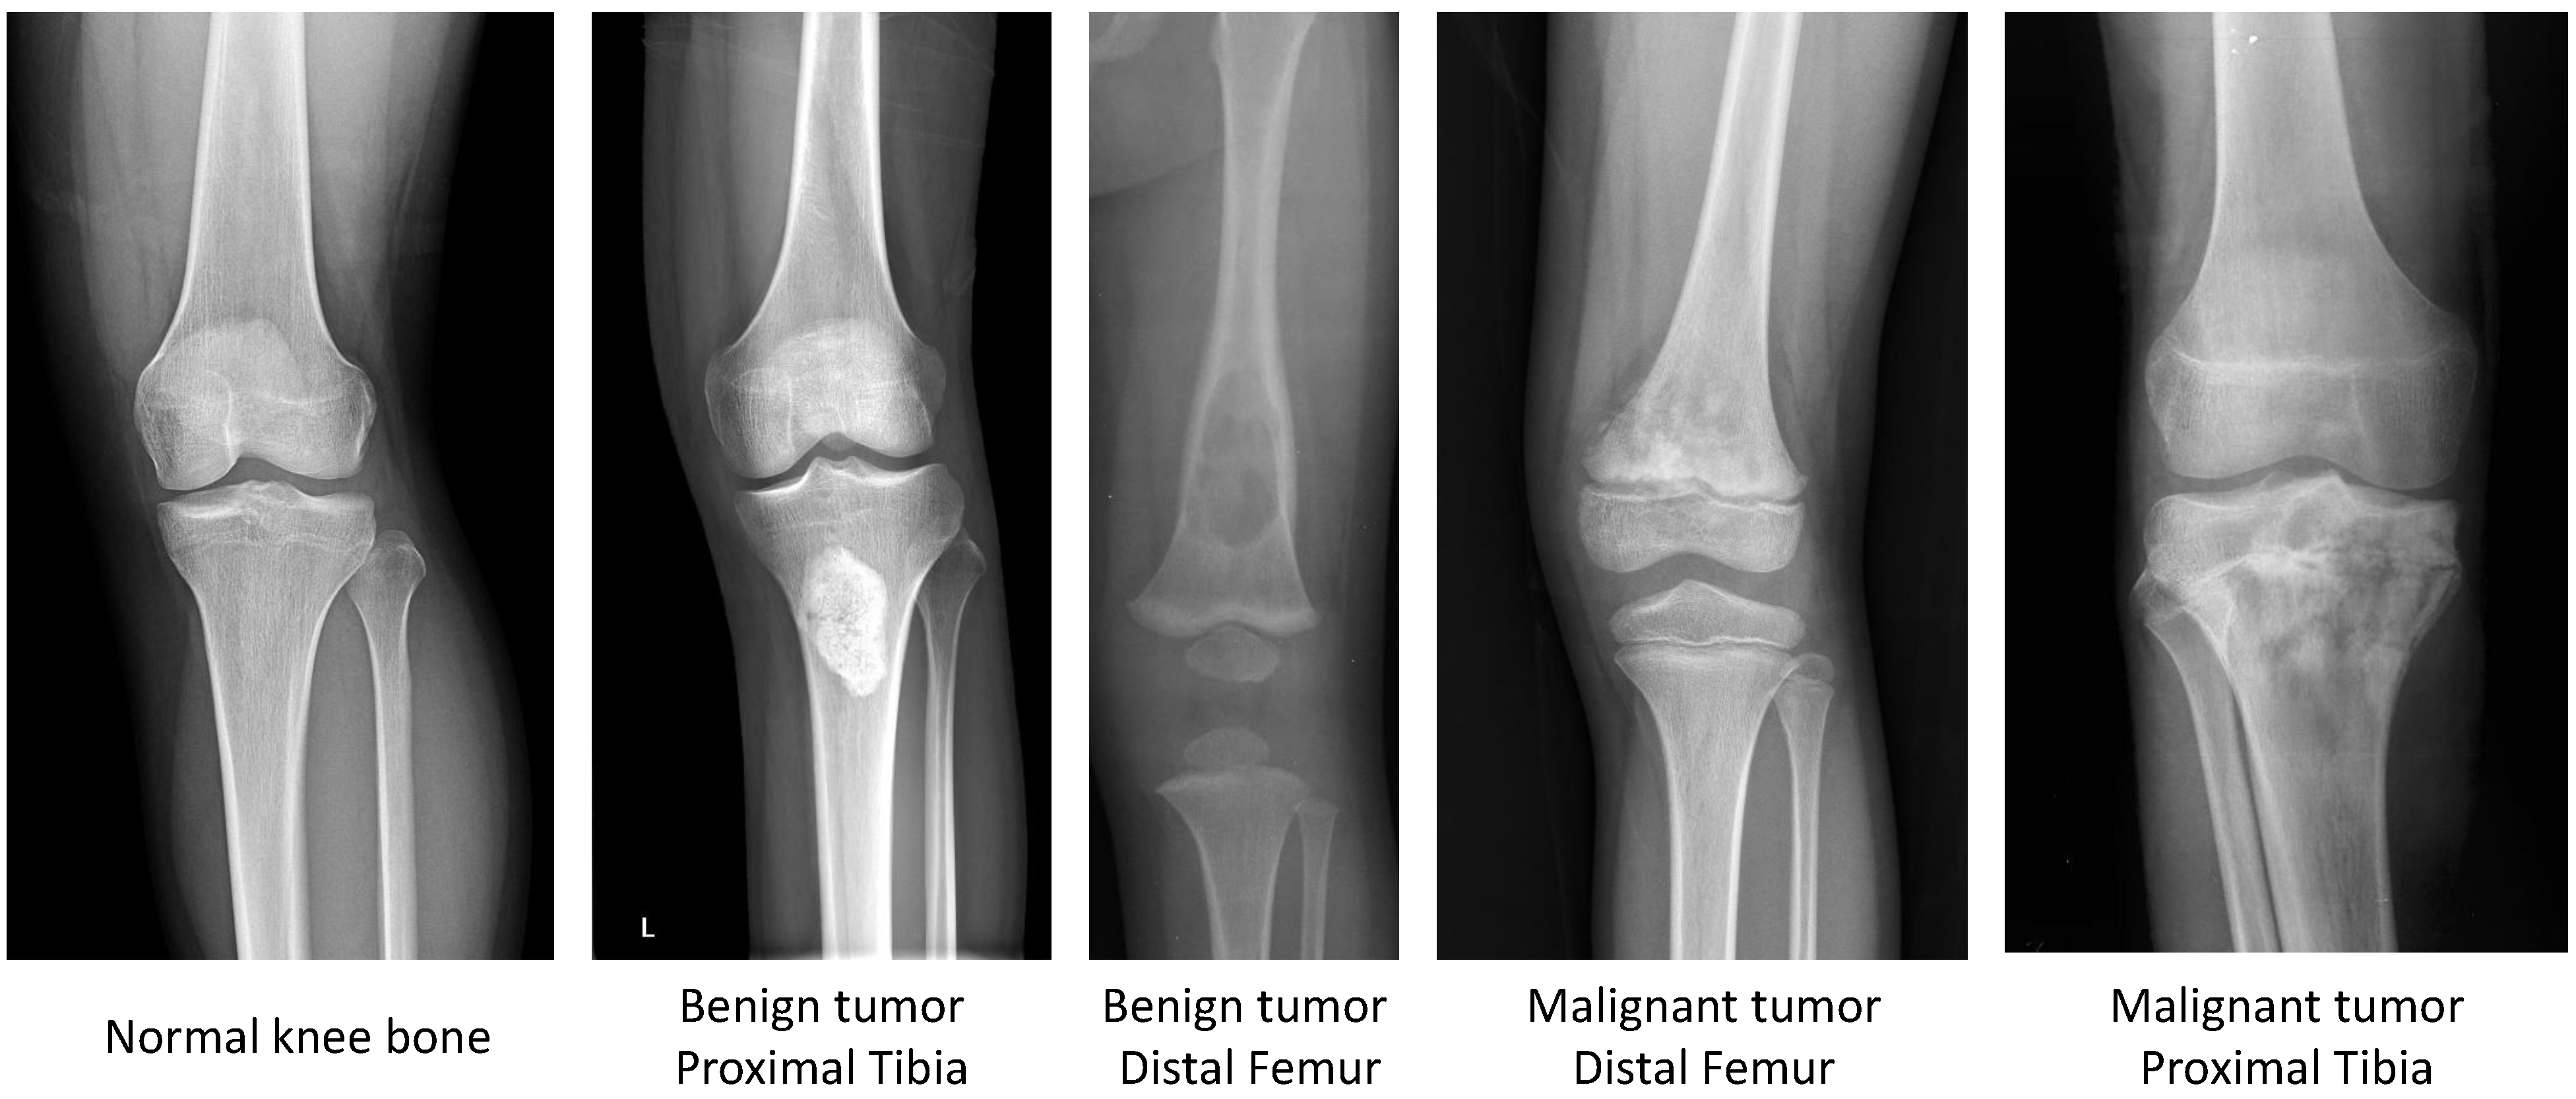

2.1. CNUH Dataset and Challenges

| Knee Region | Benign Tumor | Malignant Tumor | Normal |

|---|---|---|---|

| Distal femur | 598 | 89 | - |

| Proximal tibia | 463 | 45 | - |

| Total | 1061 | 134 | 381 |